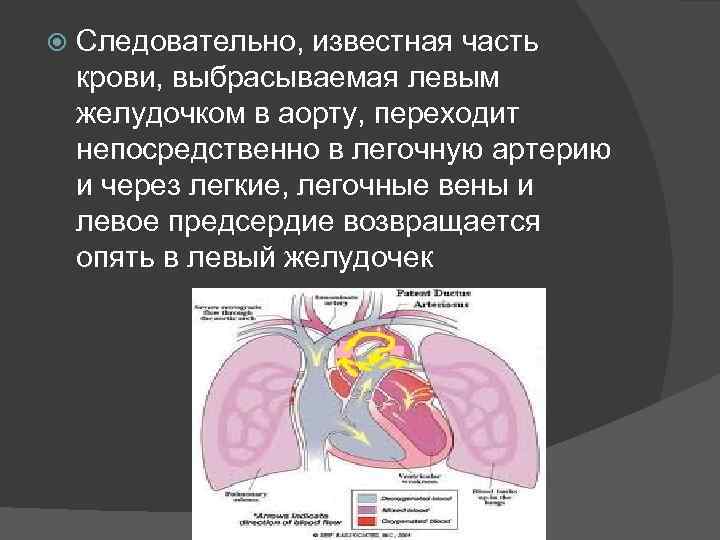

Следовательно, известная часть крови, выбрасываемая левым желудочком в аорту, переходит непосредственно в легочную артерию и через легкие, легочные вены и левое предсердие возвращается опять в левый желудочек

В результате правый желудочек компенсаторно гипертрофируется и расширяется. Расширяется и легочная артерия, которая наполняется кровью под большим давлением. Таким образом, артериальная кровь добавляется к венозной, следовательно, возникает сброс слева направо. Количество сбрасываемой крови различно в зависимости от соотношения диаметров протока и аорты.

Нередко большая часть крови, нагнетаемой левым желудочком в аорту, уходит в легочную артерию. В результате легочный кровоток преобладает над кровотоком большого круга. В связи с этим организм ребенка находится в состоянии хронического кислородного голодания, нарушается питание основных органов и тканей, в связи с чем может задерживаться физическое развитие и половое созревание.